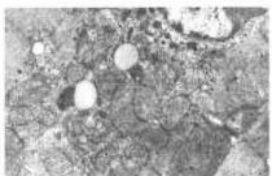

图1 对照组心肌细胞超微结构(6700) 图2 ADB损伤组心肌细胞超微结构K 9400)

图3 GcJ 组心肌细胞超微结构(x13000) 图4 GcJI 组心肌细胞超微结构(x13000)

2.1 心肌细胞的电镜观察结果 对照组:心肌细胞膜完整,肌原纤维排列有序,肌节结构清晰,线粒体在肌丝下排列规整,结构正常,核结构正常(图1)ADR损伤组:可见心肌细胞超微结构有明显改变,心肌细胞肿胀,线粒体弥漫性肿胀,增生,嵴排列稀疏,有断裂,空泡变性,基质密度降低,肌浆网扩张,次级溶酶体增多,核体积增大,核周隙增宽(图2)GCI 组:心肌细胞肿胀和线粒体肿胀有所减轻,基质密度增强,个别线粒体崎仍有改变,胞质内次级溶酶体增多(图3)GCIII组:心肌细胞结构基本恢复正常.肌原纤维排列整齐,肌节结构正常,线粒体结构恢复正常(图4)